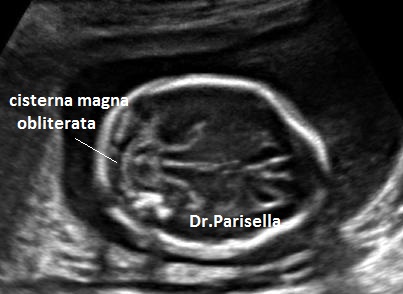

Nelle forme aperte la diagnosi ecografica prenatale si basa sui seguenti segni indiretti (1,2,3) e diretti(4,5):

1) obliterazione della cisterna magna;

I primi tre segni (segno del limone, obliterazione della cisterna magna, cervelletto a banana), c.d. segni indiretti, hanno una elevata sensibilità nella diagnosi dei difetti aperti e sono espressione della sindrome di Chiari tipo 2. Questa è la conseguenza della perdita di liquido cefalo-rachidiano attraverso il difetto spinale; la diminuzione della pressione idrostatica provoca iposviluppo della fossa cranica posteriore con conseguente erniazione del tronco encefalico e del cervelletto che si piega assumendo il classico aspetto a banana. La perdita di liquido cerebrospinale attraverso il difetto spinale provoca un aumento dei livelli di alfa-fetoproteina nel liquido amniotico e nel siero materno.